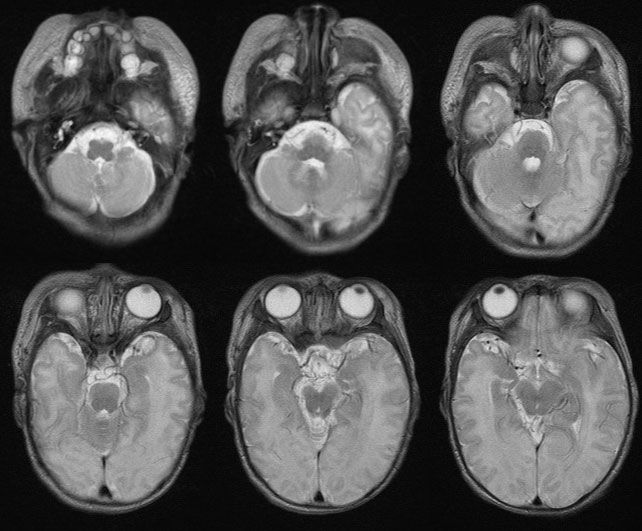

CL2757:低血糖脑损伤,测血糖为0,

低血糖脑损伤,测血糖为0,